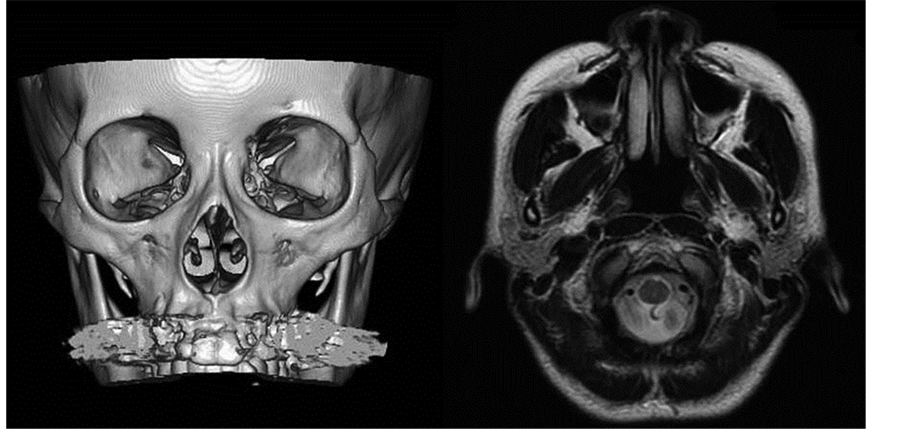

Transbronchial lung biopsy (TBLB) performed when the patient was 25 showed epithelioid cell granuloma that was confirmed as sarcoidosis. Traveling infiltration shadows in the lung were followed closely without treatment. She developed nasal congestion and rhinitis at the age of 42 years. Her nose began to show the saddle nose deformity at the age of 43 years. Secondary recurrent multiple chondritis was suspected and steroid hormone therapy was administered. Consecutive close investigations confirmed that the diagnosis was not established without sarcoidosis. Her nose deformity progressed and rhinoplasty was planned. Preoperative computed tomography showed that the nasal bone was intact. Preoperative magnetic resonance imaging showed that the alar cartilages were intact but the nasal septum was atrophied and absorbed (Figure 1). Our patient was 45 years of age at the time of surgery (Figure 2).

Figure 1. Preoperative computed tomography showed that the nasal bone was intact (left). Preoperative magnetic resonance imaging showed that the alar cartilages were intact but the nasal septum was atrophied and absorbed (right).